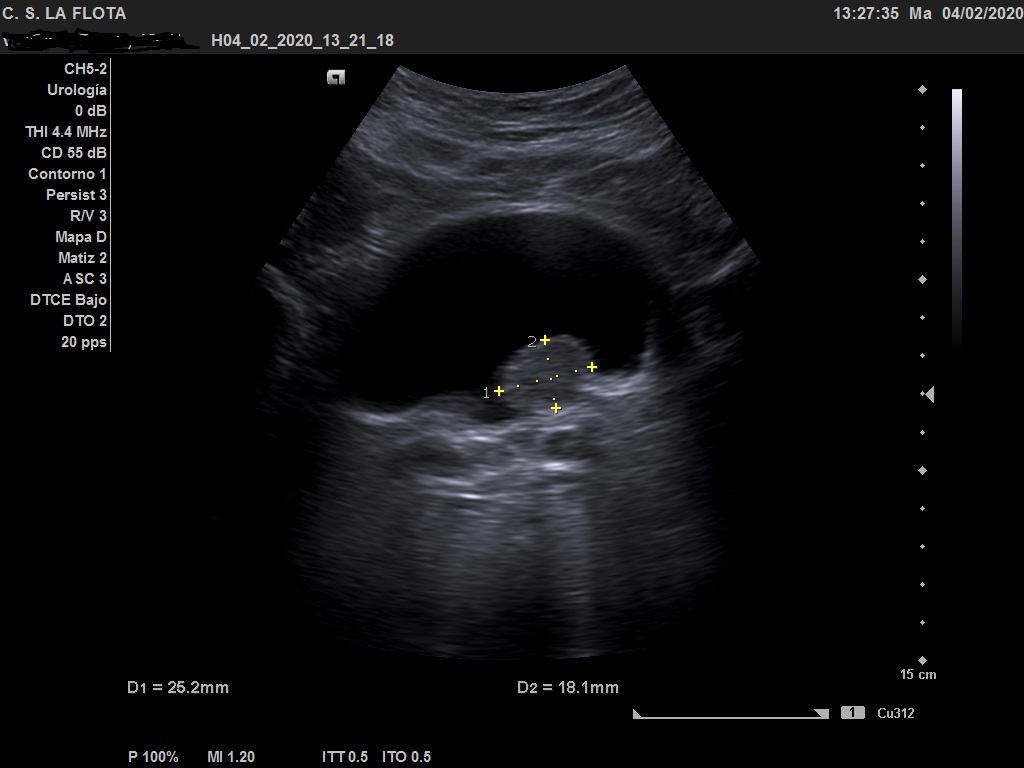

Ecografía clínica: riñones de tamaño y morfología normal, con buena diferenciación corticomedular y sin dilatacion de vias. En vejiga lesión polipoidea  de 25*18 mml.